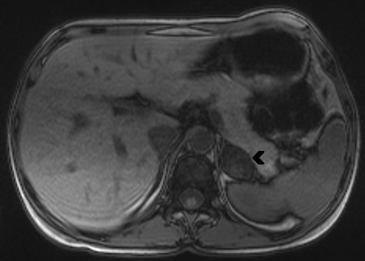

Figura 23. Carcinoma suprarrenal derecho. Corte axial de resonancia magnética ponderado en T2 con saturación grasa (a) en que se demuestra una masa suprarrenal derecha con áreas hiperintensas en su espesor probablemente determinadas por necrosis (flecha) y corte coronal en secuencia TRUFISP (b) en que se observa un trombo tumoral que expande el lumen de la vena cava inferior (cabeza de flecha).Puede también presentar invasión directa de otras estructuras vecinas, como riñón, páncreas, bazo y diafragma.